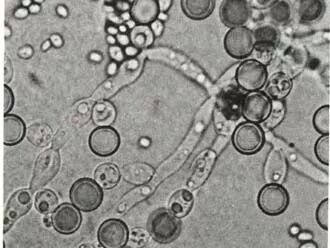

韩国汇恩斯公司品质保证部门针对假针头的市场乱象专门做了一项关于得玛莎中国假货针头的无菌实验。

实验结论如下:实验表明假货针头无菌状态不成立。鉴定菌种的结果显示,确定为吉利蒙念珠菌。其是一种真菌类病原性微生物,当人体免疫力低下时,很有可能继发感染,并且这种真菌对抗真菌药物敏感性较低,在治疗上有一定困难。因此请勿使用假货针头。